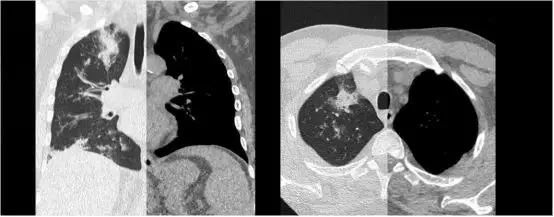

1秒内扫描全身+自由呼吸无禁忌成像

胸腹联合扫描